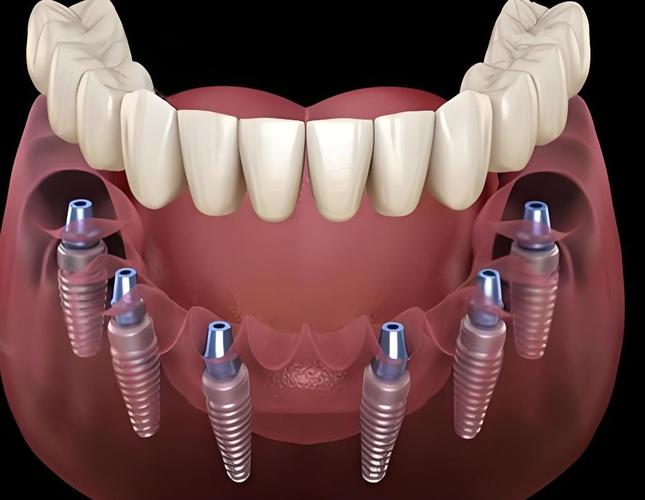

植牙图中,4颗种植体的分布是技术核心:前牙区(侧切牙位置)植入2颗种植体,通常垂直于牙槽骨,提供初期稳定性;后牙区(磨牙位置)植入2颗种植体,以30°-45°角度倾斜植入,这种设计有两个关键作用:一是避开上颌窦(上颌后牙区)或下牙槽神经管(下颌后牙区)等重要解剖结构,避免植骨手术;二是利用倾斜角度增加种植体与骨组织的接触面积,并通过力学分散咬合力,减少种植体承受的杠杆力,提升长期稳定性。

植牙图中可见,种植体上方通过基台连接固定桥牙冠,前牙区垂直种植体通常使用直基台,后牙区倾斜种植体则使用角度基台(如17°或30°基台),确保基台长轴与牙冠长轴一致,避免侧向力损伤种植体-骨结合界面,牙冠部分多采用全瓷材料(如氧化锆),通过CAD/CAM技术精准制作,形态、颜色与自然牙高度匹配,植牙图中会标注咬合接触点的位置,确保前牙轻接触、后牙多点均匀受力,实现功能与美观的统一。